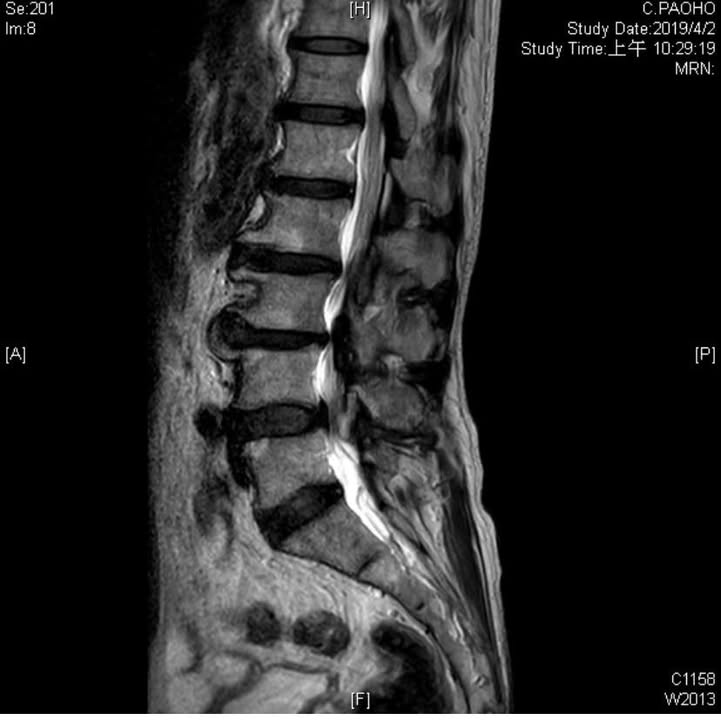

八十多歲的莊伯伯腰痛半年多,抱怨走路大約一個路口五十公尺內就不太舒服,雙腳都麻,坐著不會麻,坐位轉成站位有一股熱氣往大腿後側,腰非常痠痛 ,走路明顯往前彎與傾斜,在高雄大醫院拍過MRI 核磁共振證實腰椎管嚴重狹窄合併椎間盤退化突出壓迫神經(如下圖),看過數個大醫院的醫師都建議開刀!但是老先生心臟問題不穩定且有裝支架,變成醫師不太敢開刀!所以還是保守療法復健為主,但效果就是不好,也不可能天天吃止痛藥吧!經過友人介紹特別從高雄北上接受腰椎整合針刀療法,第一次來門診時老先生很明顯彎腰走路很痛苦,看過片子後又發現老先生的腰椎多裂肌跟腰大肌有萎縮現象,這是一個很難的案例,跟老先生說先安排四次治療如果有改善就走完一整個療程,如果沒改善可能還是開刀為主

可以的!透過核磁共振與肌肉骨骼超音波都看的到 ,在個案中發現莊伯伯多裂肌幾乎萎縮一半,被脂肪組織白色部分填充, 以下圖片是幾個多裂肌萎縮的情況從正常 中度 重度萎縮